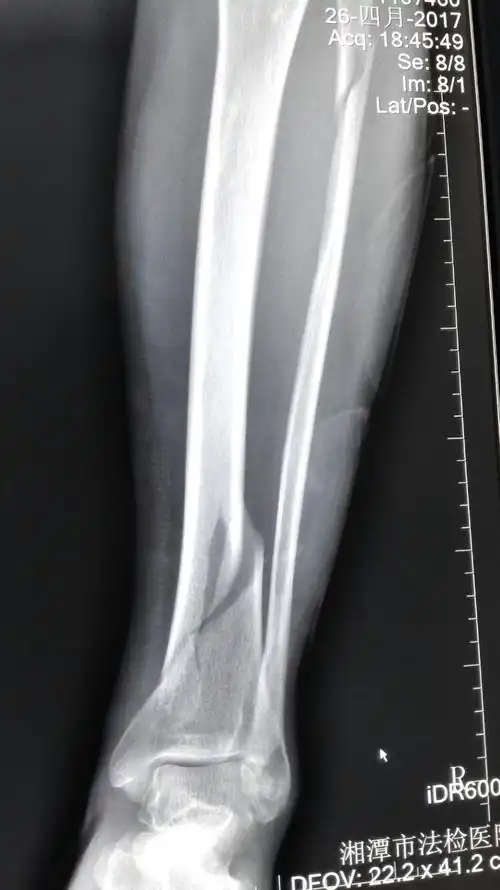

胫骨下段腓骨上段螺旋形骨折的治疗方案